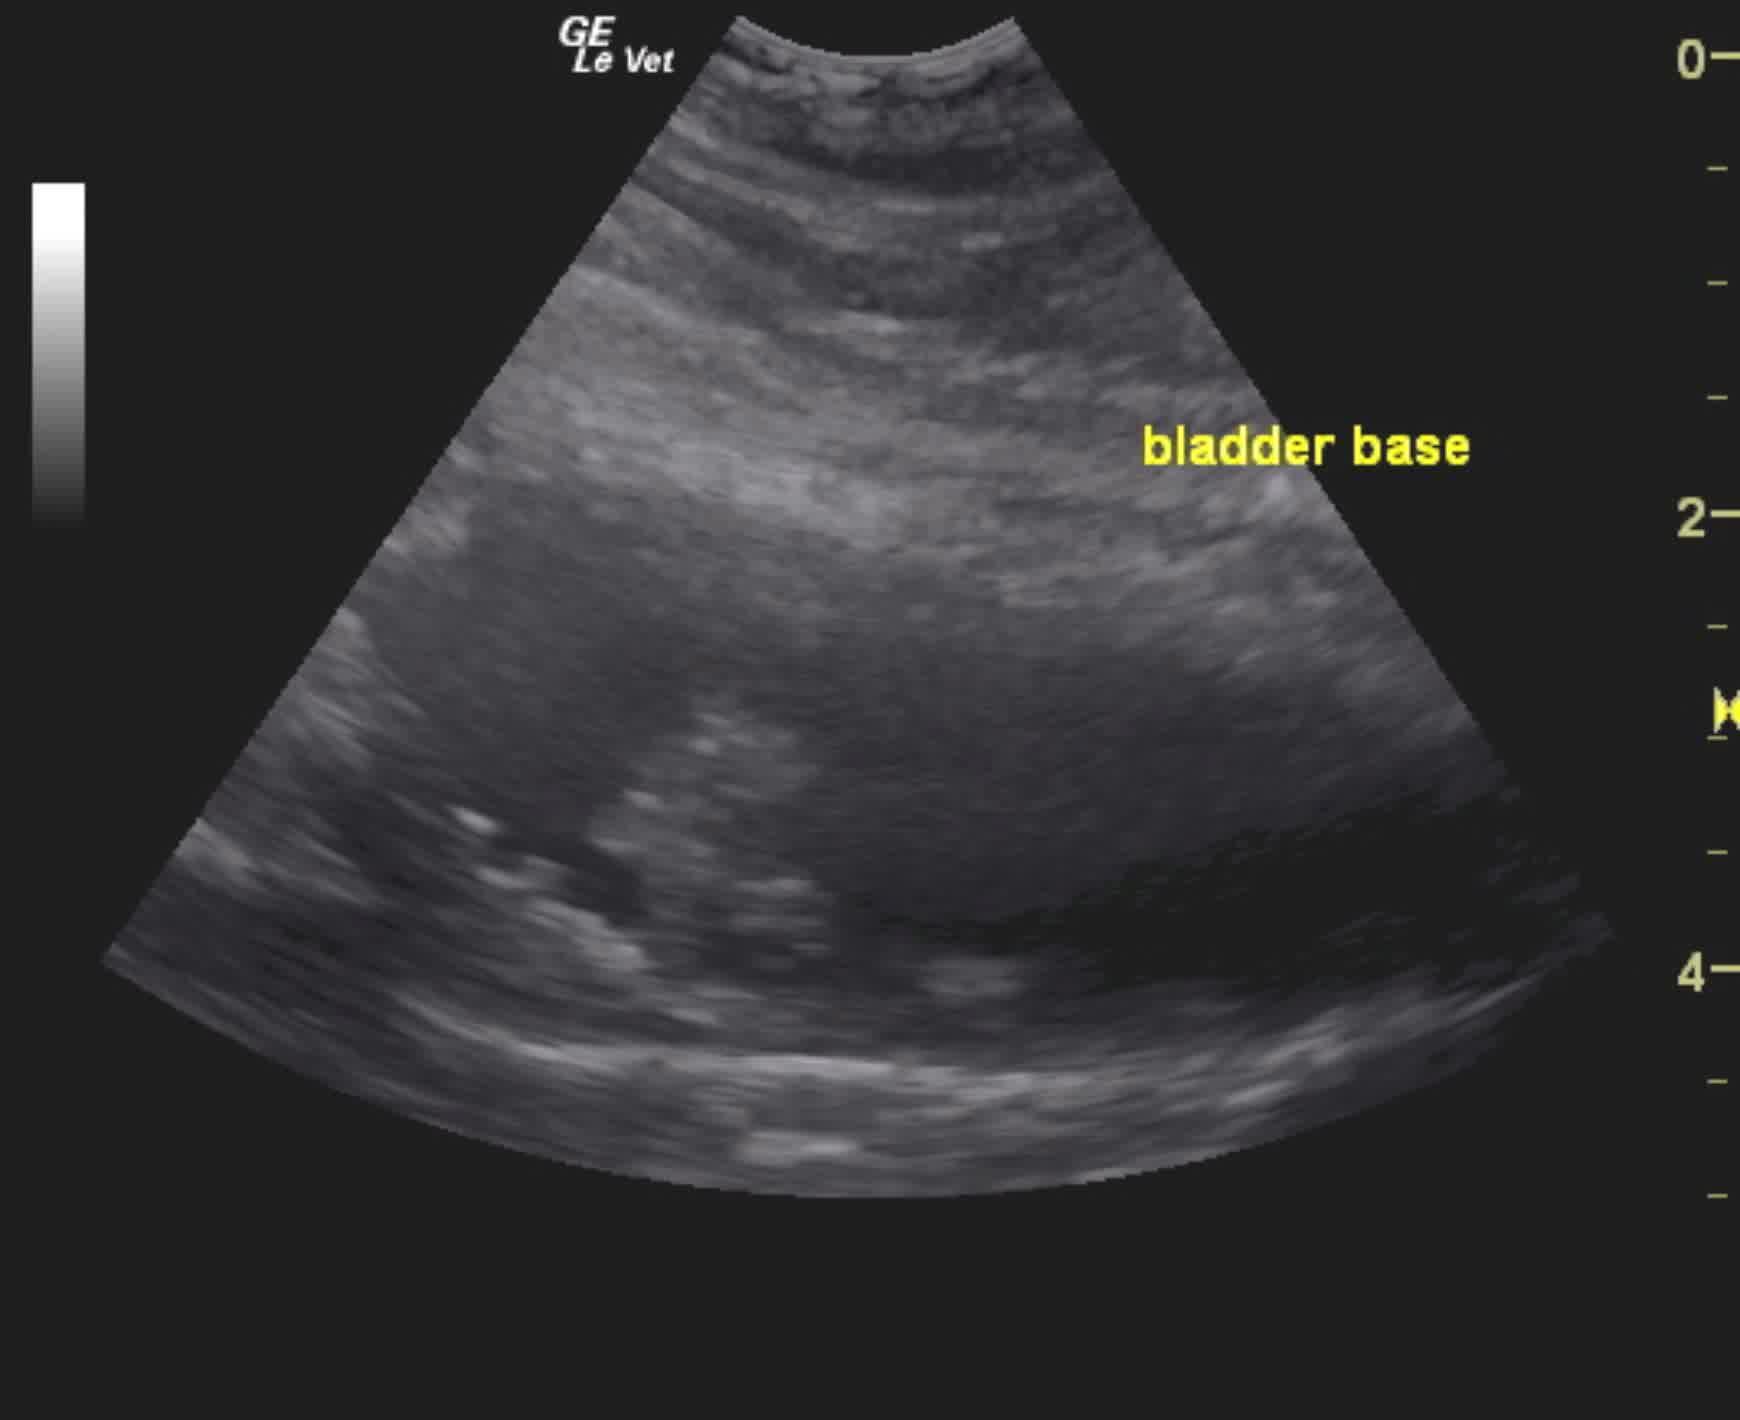

A 12-year-old Shepherd mix dog was presented for evaluation of an 18-month history of urinary incontinence and hematuria. Urinalysis showed normal specific gravity, hematuria, and pyuria.

A small, non-shadowing concretion with polypoid apical wall changes and chronic cystitis pattern. Transitional cell carcinoma and polypoid hyperplasia are both possible. Small mobile calculi.

The urinary bladder presented a small, non-shadowing concretion that measured 0.5 cm; the bladder also had polypoid apical wall changes and chronic cystitis pattern. Multiple, mobile small calculi were noted in the bladder with shadowing. Urethral calculi were also noted.

Chronic cystitis, cystic calculi, and possible bladder mass

The area of the mass or polyp appears resectable with resection of the cranial half of the bladder.